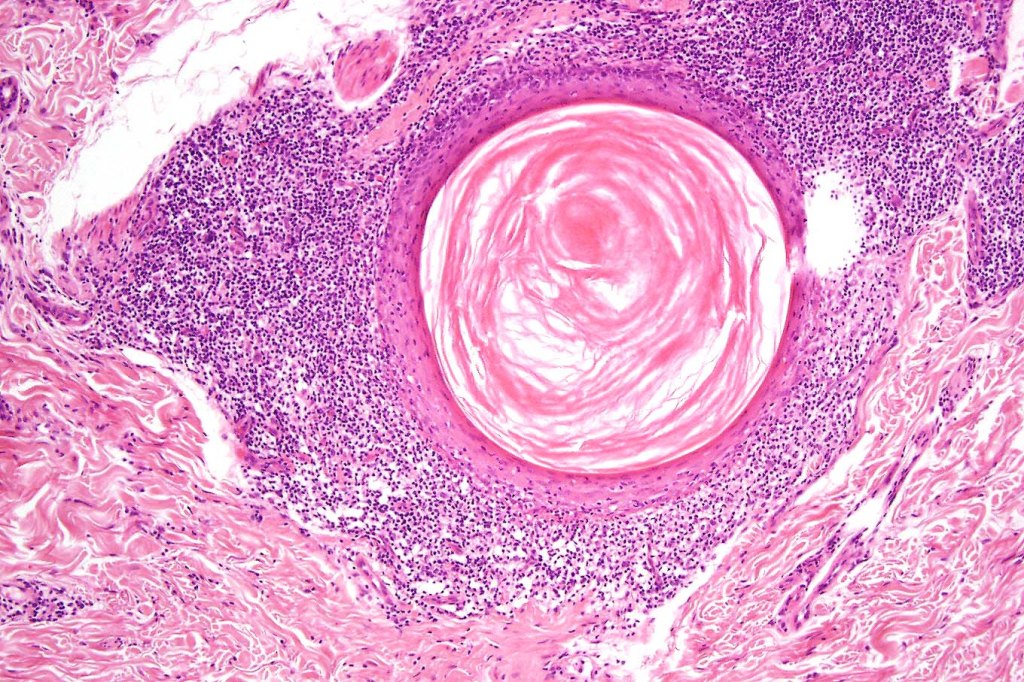

Histological features

•Follicular infiltration by atypical lymphocytes & Sézary cells

•Granulomatous inflammation secondary to follicular destruction